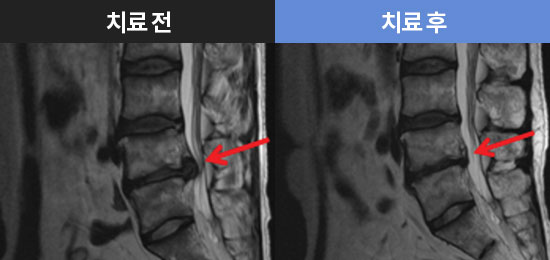

CHAMJALHAM MRI로 보는 치료결과

허리 디스크&협착증 치료 사례

허리디스크 치료 사례

허리디스크 3주 치료 사례